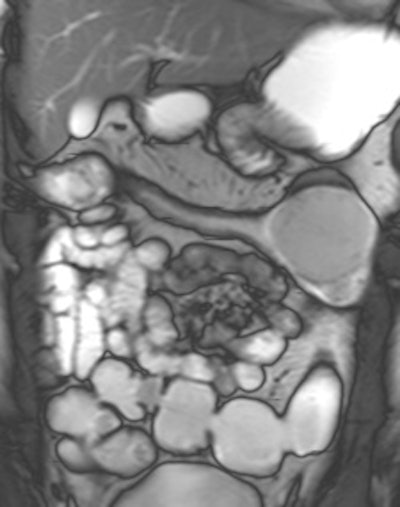

MRE can distinguish between inflammatory, stricturing and penetrating disease, and can be performed prior to video capsule endoscopy (VCE) in excluding strictures where VCE can then be used to detect subtle mucosal disease. In combination with blood and fecal biomarkers and endoscopy, MRE can assist the treating clinician in distinguishing between inflammatory stenoses amenable to medical therapy and fibrostenotic disease requiring surgery, she wrote in an article published online on 16 March by Insights into Imaging.

MRE is a particularly useful in the assessment of treatment response. When MRI is performed during an acute relapse and then in remission, a reduction in both mural contrast enhancement and in mural thickness in affected segments is seen, but luminal stenosis may persist. Biologics such as infliximab and adalimumab have been used to treat patients with Crohn's disease resistant to other therapies with mucosal healing as a key treatment goal.

"From our experience, MRE can be used to show a significant reduction in inflammatory activity (as demonstrated by reduced mural thickening, edema, and enhancement) following treatment with such agents. DWI may have a role in response assessment with a predicted decrease in the degree of restricted diffusion. However, as yet there are no published papers on this subject," explained Griffin.